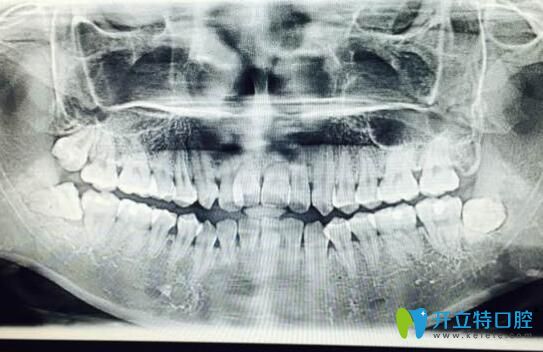

案例二:牙根短做正畸5個(gè)月自白

其實(shí)做正畸之前,我也非常擔(dān)心,但是變美的沖動(dòng)大于一切,所以在認(rèn)真的篩選了和醫(yī)生之后,我開始了我的正畸之旅。

牙根短做正畸5個(gè)月自白

我已經(jīng)戴牙套5個(gè)月了,下個(gè)月還要打種植釘,而且迄今為止都比較好。

牙根短做了牙齒矯正

到現(xiàn)在我還是不后悔。沒有覺得牙齒有松動(dòng)。為自己悄悄變美每天都很高興。